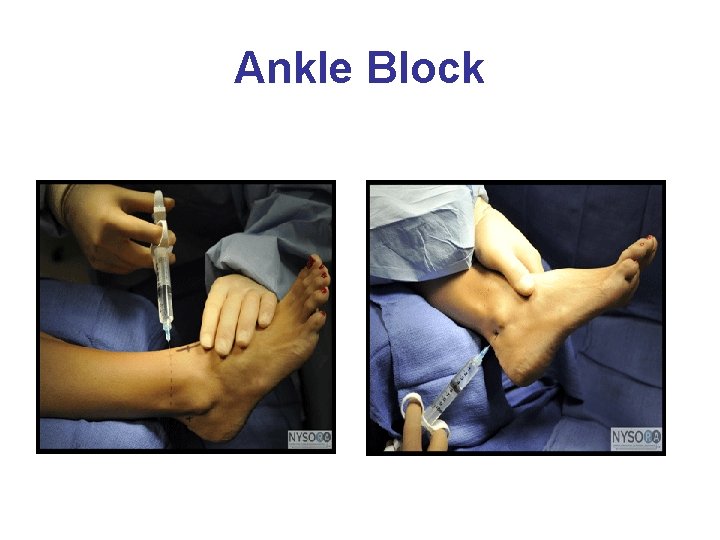

Ankle Block • Patient is positioned in a supine position. Elevation of the patients calf permits the various insertion sites (ring-like) to be more easily accessed. • An uncomfortable block requiring 5 different injections • Epinephrine is contraindicated. Potential arterial vasoconstriction may lead to foot and/or toe ischemia secondary to the lack of collateral circulation at that location.

Ankle Block